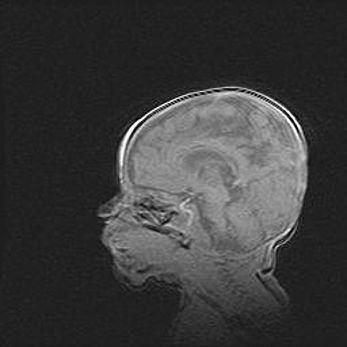

Неполная лизэнцефалия (пахигирия). Открытая гидроцефалия.

Возраст: 17 дней

Вес: 3110 г

Пол: мужской

Окружность головы: 33,5 см

Срок гестации: 35-36 недель

Лизэнцефалия—недоразвитие корковой пластинки и мозговых извилин в результате нарушения миграции нейронов коры. Поверхность мозговых полушарий гладкая. Микроскопически выявляется отсутствие нормальных слоев коры и скопление групп нейронов в подкорковом белом веществе.

Пахигирия—уменьшение числа вторичных извилин. В пораженном полушарии нервные клетки образуют толстый недифференцированный слой с неправильно расположенными нервными волокнами и группами гетеротопных клеток. Нервные клетки незрелые. Белое вещество истончено. При этом нередко аномально развит корково-спинномозговой путь.